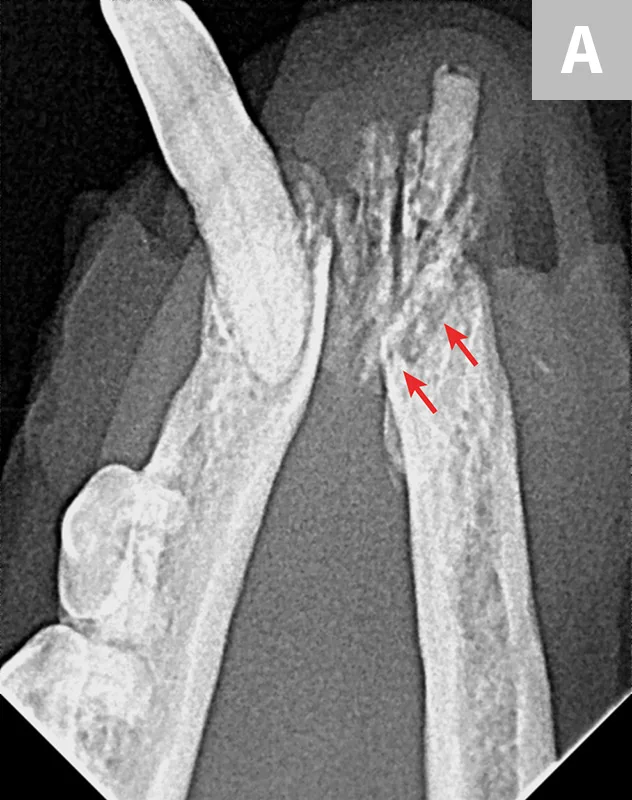

Dental X-ray with arrows pointing to root fractures of the 4th maxillary premolar in a dog.

FIGURE 1

Fracture of the mesiobuccal and distal roots (arrows) during extraction of the left maxillary 4th premolar tooth in a dog